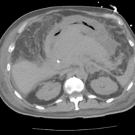

A 70-year-old man with a history of hyperlipidemia, benign prostatic hyperplasia, and cholecystectomy presented to the emergency department with abdominal pain, vomiting and abdominal distention for the...